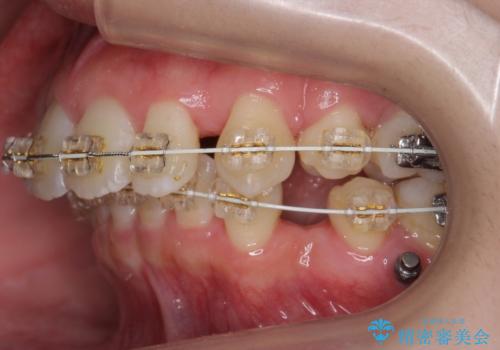

左上の小臼歯が込み合っており、虫歯治療が厳しい状態でした。

矯正治療をおすすめし、ちょうど虫歯がひどい歯は抜歯して前歯を下げました。

下顎の大臼歯が前に倒れこんでいたため、矯正用ミニスクリューで後ろに起こしています。